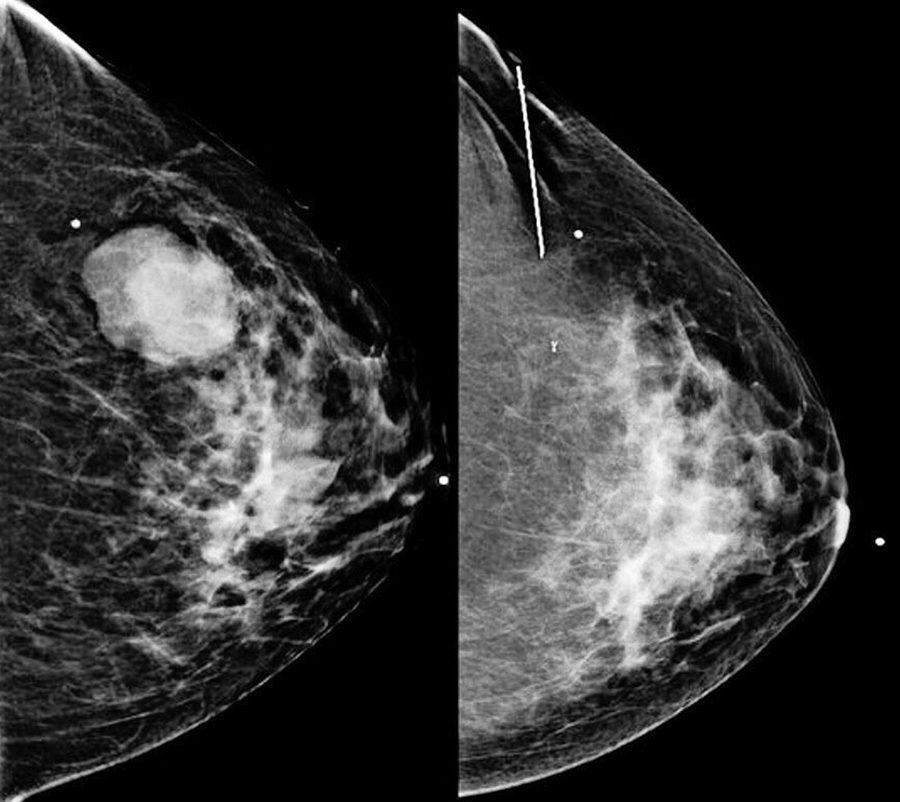

La terapia de protones para el cáncer de mama puede evitar daño en el corazón

El ensayo compara la cardiotoxicidad de la administración de radioterapia basada en protones y en fotones a la mama/la pared torácica y los ganglios linfáticos